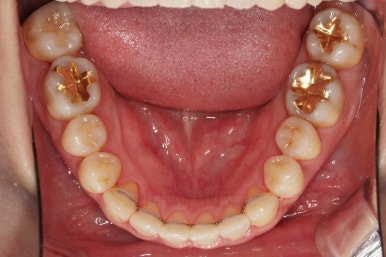

아랫니는 중앙선을 맞추기 위해서 미니스크류를 이용해 한 쪽으로 당기는 중이고요.

이 과정에서 아랫니들이 약간은 뒤로 들어가져서 아랫입술 부위의 돌출감을 아주 약간은 줄일 수 있습니다.

윗니 임플란트 할 자리는 적절히 계속 맞춰줍니다.

중앙선도 점점 맞아지고 있어요.

임플란트 할 공간도 여유롭게 마련이 되었네요.